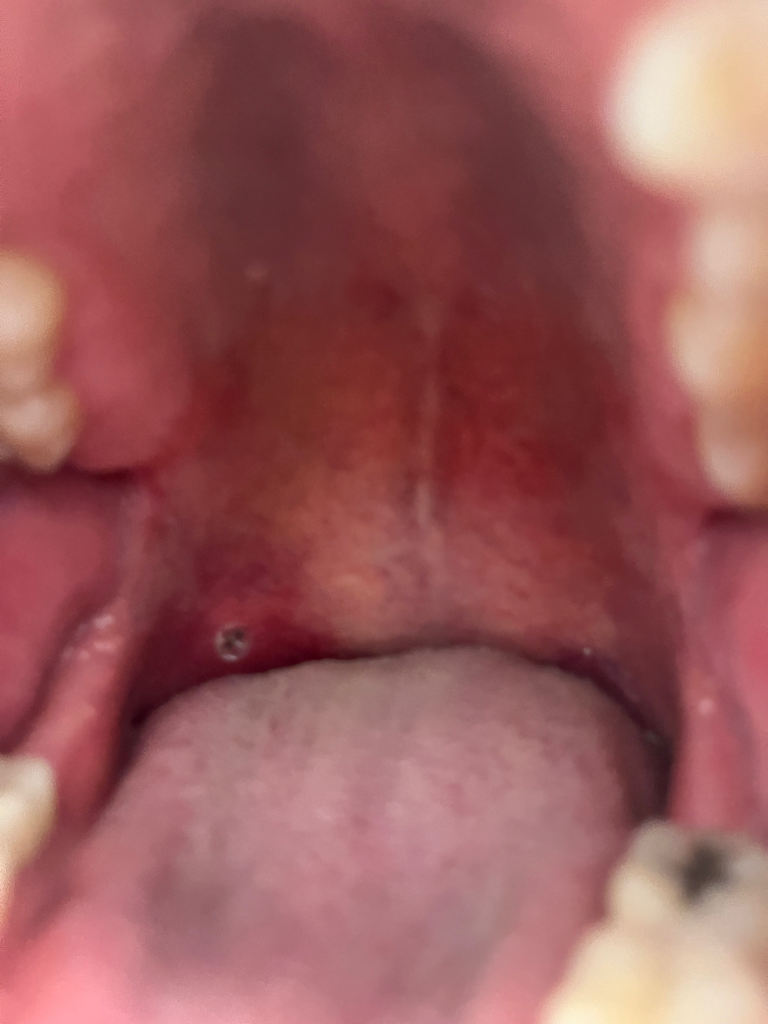

이거 구강암인가요? 구내염인가요?

어제 부터 입천장에 구내염의 흰색이 나다. 오늘 알보칠로 치료하였고, 저녁에 약을 바르기 위해 발랐더니 흰색 껍질이 벗겨지면서 현재 사진과 같이 흰색 + 검정반점이 안에 있는데요 ㅠㅠ

치료하고 난 후의 병변이라면 구내염입니다. 구내암일 가능성은 거의 없어요. 그냥 지켜보시면 됩니다.